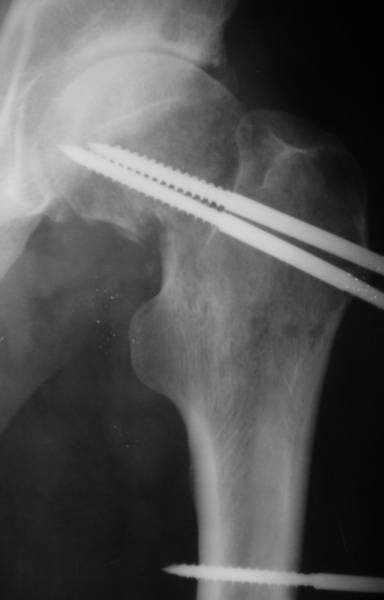

Насчет 8 см согласен с А.Н. Челноковым, это наверное ортопедическое за счет приводящей, сгибательной контрактуры и, возможно, колена. на ликвидацию укорочения у нас обычно уходит около 2-х нед. снимки в приложении, возможно не очень показательные, но других с ходу не нашел, завтра еще поищу.

Еще пара фото, ситуация несколько иная, задачи те же, открытое вправление застарелого вывиха в 2002, молодой возраст. Сейчас госпитализирована для эндопротезирования.

По рентгенограммам укорочение не более 4 см, остальное возможно за счет контрактуры. Опыта с низведением аппаратом Илизарова нет, но мы одномоментно такие укорочения корригировали вполне успешно (в год 5-10 именно таких и проходит). Лишние этапы пожалуй только будут способствовать инфекции. Доступ чаше применяем передне-наружный, а вот протез наверное поставили бы здесь на цементе - остеопороз выражен.

Больного прооперировали на прошлой неделе (цементный протез, цемент с гентамицином). Использовали задне-боковой доступ. В области перелома подвижности практически не было, так что тему сообщения уместно заменить на "неправильно сросшаяся шейка". И в головке, и во впадине

были значительные дегенеративные изменения, так что ни биполяр, ни остеосинтез тут неуместны (хотя это предлагали в ortopod'е). После релиза удлинили ногу на 3 см. Дальше удлинять побоялись из-за

натяжения седалищного нерва, хотя в принципе можно было бы еще 15-20 мм нарастить. По послеоперационной рентгенограмме анатомическое укорочение порядка 15 мм. Клинически при ходьбе - 4 см, но это за счет перекоса таза.

The patient underwent cemented THR on last week. Postero-lateral approach was used. There was only minimal motion at the fracture site and we had to cut the femoral head with oscillating saw. The femoral head was deformed with it's cartilage completely absent in some areas.

Acetabulum showed gross degenerative changes, especially in superior rim. So I think it was right choice not to do ORIF in this case. After some soft tissue release we've lengthened the leg up to 3 cm. Further lengthening was possible but we stopped at that moment due to tension of n. ischiadicus. Now patient walks with crutches. Leg length discrepancy is about 4 cm due to pelvic tilt (discrepancy on post-op x-ray is 15 mm).